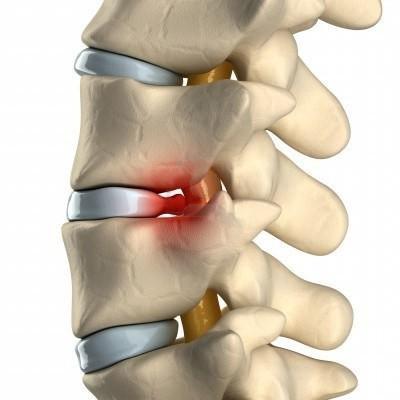

Межпозвоночная грыжа

Поясничные грыжи обычно находятся между третьим, четвертым и пятым поясничными позвонками и между пятым позвонком и крестцом. Зачастую грыжей защемляются нервы, ведущие в нижние конечности. Боль при межпозвонковых грыжах острая. Больному тяжело нагибаться, вставать, порой даже лежать на ровной поверхности.

- Остеохондроз – процесс разрушения межпозвоночного диска, при котором позвонки сближаются, защемляя нервы. Обостряется сезонно, после гиподинамии, нагрузок. Боли длительные, средней интенсивности, разлитые. Схожая симптоматика, обычно, наблюдается и в суставах других групп;

- Грыжа, протрузия межпозвоночного диска – выход диска или его содержимого за пределы позвоночного столба, в спинномозговой канал. Происходит сдавливание большого количества нервной ткани, потому кроме очень интенсивных болей наблюдаются онемения ног, гипертонус, спазм мышц в них, их слабость;